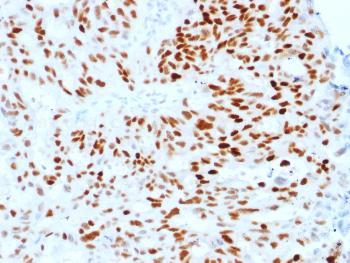

Fig. 1: Formalin-fixed, paraffin-embedded human Endometrial Carcinoma stained with Estrogen Receptor alpha Mouse Monoclonal Antibody (ESR1/1904).

Western Blot (1-2ug/ml); ,Immunohistochemistry (Formalin-fixed) (1-2ug/ml for 30 minutes at RT),(Staining of formalin-fixed tissues requires heating tissue sections in 10mM Tris with 1mM EDTA, pH 9.0, for 45 min at 95°C followed by cooling at RT for 20 minutes);